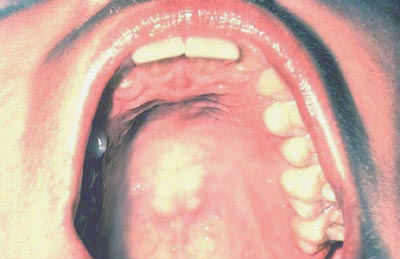

| Con la lengua aún elevada, inspeccione el piso de la boca buscando cambios de color, textura, hinchazones u otras anormalidades en la superficie. |

| Con la boca totalmente abierta y la cabeza del paciente echada hacia atrás, presione suavemente la base de la lengua con un espejo dental. Primero inspeccione el paladar duro y luego el paladar blando. |

| Examine el paladar blando, úvula, trígono retromolar y los pilares anteriores.. |